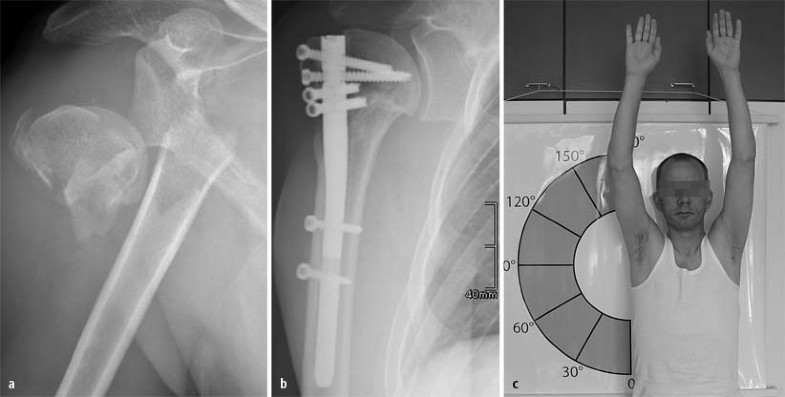

Der 39-jährige Patient erlitt bei einem Skisturz eine 4-Segment-Luxationsfraktur des rechten proximalen Humerus (Abb. 6). Trotz erheblicher Dislokation wurde aufgrund des jungen Patientenalters die Indikation zum Kopferhalt gesehen. Es wurden eine limitiert offene Reposition und Stabilisierung mit dem T2-PHN unter Verwendung des zentralen Nageleintrittspunkts und aller 4 Verriegelungsschrauben zur Fixierung der Tuberkel vorgenommen.

Unter dem oben beschriebenen Nachbehandlungsschema zeigte sich bereits ein halbes Jahr nach dem Unfall ein hervorragendes Behandlungsergebnis. Ein Jahr nach dem Unfall wies der Patient einen Constant-Score von 97 auf. Eine Humeruskopfnekrose war auch im Verlauf nicht feststellbar.

Männlicher Patient, 39 Jahre, a 4-Segment-Luxationsfraktur nach Skisturz, b a.-p. Röntgenkontrolle nach 1 Jahr, c Beweglichkeit nach 1 Jahr